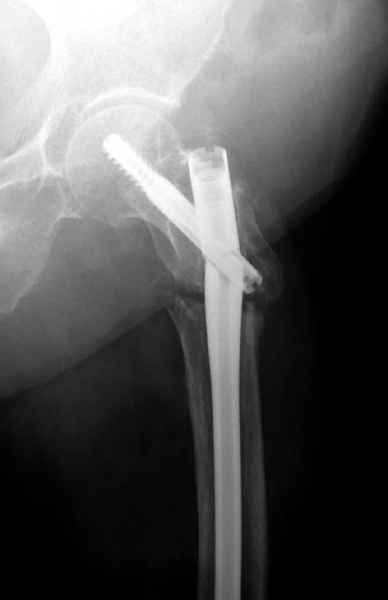

Ятрогенный подвертельный перелом

Из истории, травму получила в сентябре 2007 года и по поводу перелома шейки бедра больная была проперирована тремя каннюлированными шурупами с явным нарушением технологии установки шурупов. Внизу вместо одного шурупа имеется два, что привело к стрессу латерального кортекса.

Через месяц по поводу ятрогенного подвертельного перелома сделана фиксация длинной Гамма 3.

Установлен без проксимальной блокировки? (set screw).

В данный момент имеется несостоятельность конструкции и ложный сустав.

Передвигается с помошью костылей, конечность укорочена на 2 см.